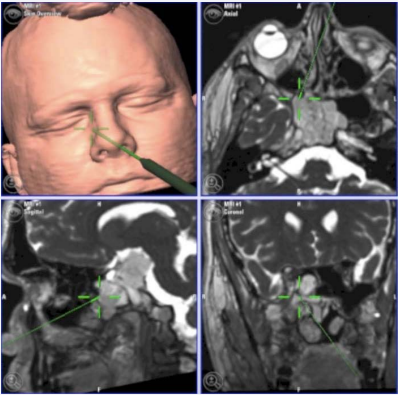

Chordomas are slow-growing malignant tumors that arise from notocord remnants along the length of the neuraxis. These neoplasms have an incidence about 0.08 per 100,000 and they are more frequent in fourth and fifth decades of life. Skull base appears to be responsible for about 40% of all chordomas and the clivus is commonly involved location [25, 26]. Chordomas are locally aggressive and tend to recur after surgical resection, however they rarely metastasize to distant sites. Patients with Clival chordoma usually present with headache and diplopia, secondary to abducent nerve palsy. Progressive compression and local invasion of the lesion may lead to other lower cranial nerve deficits [7, 26]. CT-scan typically shows an expansive soft-tissue mass arising from the intraosseous part of the clivus and causing extensive lytic bone destruction and showing intratumoral calcifications. Surrounding sclerosis is not common. There is heterogeneous enhancement following contrast administration. At MRI, chordomas are isointense to slightly hypointense on T1- weighted images and hyperintense on T2-weighted images, with areas of decreased signal intensity due to calcifications (Figure 2).

Figure 2 Intra-operative images of a clivalchordoma on neuronavigation system.

Figure 2: Intra-operative images of a clivalchordoma on neuronavigation system.

Contrast addiction reveals a strong enhancement in both techniques, distinguish it from Ecchordosisphysaliphora (EP) [26-28].

Chondrosarcomas are malignant mesenchymal tumors composed of cartilage-producing cells. They can be developed de novo, resulted of a malignant transformation of a chondroma or can be associated with other osseous diseases. These tumors are more frequent in men in the fourth decade of life. Intracranial chondrosarcomas are more common in the skull base, arising from chondrocytes within cartilaginous remnants in petroclival and spheno-occipital synchondroses. They represent about 6% of skull base neoplasms and they constitute a challenge, given their location. Despite they are overall slow growing, they manifest local aggressiveness. Skull base chondrosarcomas usually present with insidious onset headache and cranial nerve palsies such as hoarseness, dysphagia, diplopia, facial dysesthesia or hearing loss [29,30]. CT findings include enhancing soft-tissue mass with a calcified matrix, bone erosion and destruction and a sharp zone of transition to normal tissue. CT-scan is useful for detecting subtle calcifications in the matrix when the diagnosis is in doubt. On MRI, lesions are hypointense on T1-weighted images and hyperintense on T2-weighted images, relative to the brain (Figure 3).

Figure 3 Coronal and axial T2-weighted images showing an extensive Petroclival condrosarcoma.

Figure 3: Coronal and axial T2-weighted images showing an extensive Petroclival condrosarcoma.

The contrast enhancement is very strong. Neoplasms commonly exhibit heterogeneous internal areas of decreased signal, corresponding to internal calcifications [31].